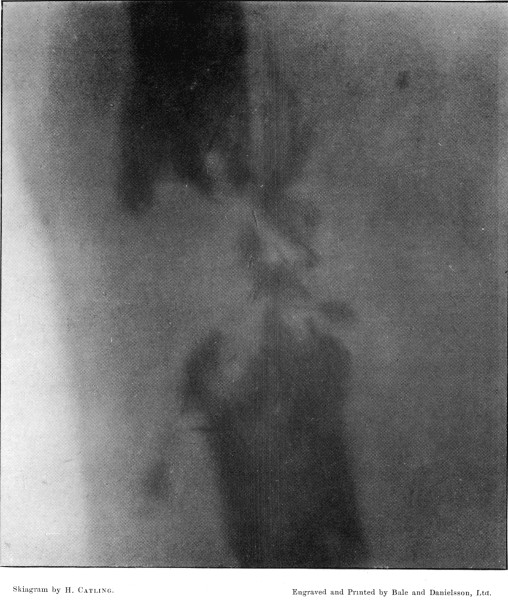

19. Oblique Comminuted Fracture of the Tibia210

20. Transverse Fracture of the Tibia212